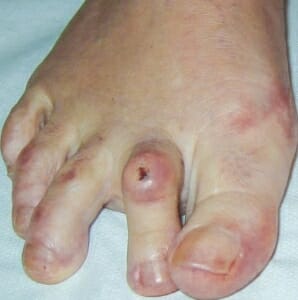

Abb. 1

PIP Hammerzehe mit Rötung und Einblutung der Haut über dem Zehen-Mittelgelenk, zusätzliche Abweichung der 2. Zehe nach innen und der 3. Zehe nach außen. Schwellung und Schmerzen über dem Zehengrundgelenk 2 u. 3 bei einem Prädislokationssyndrom.